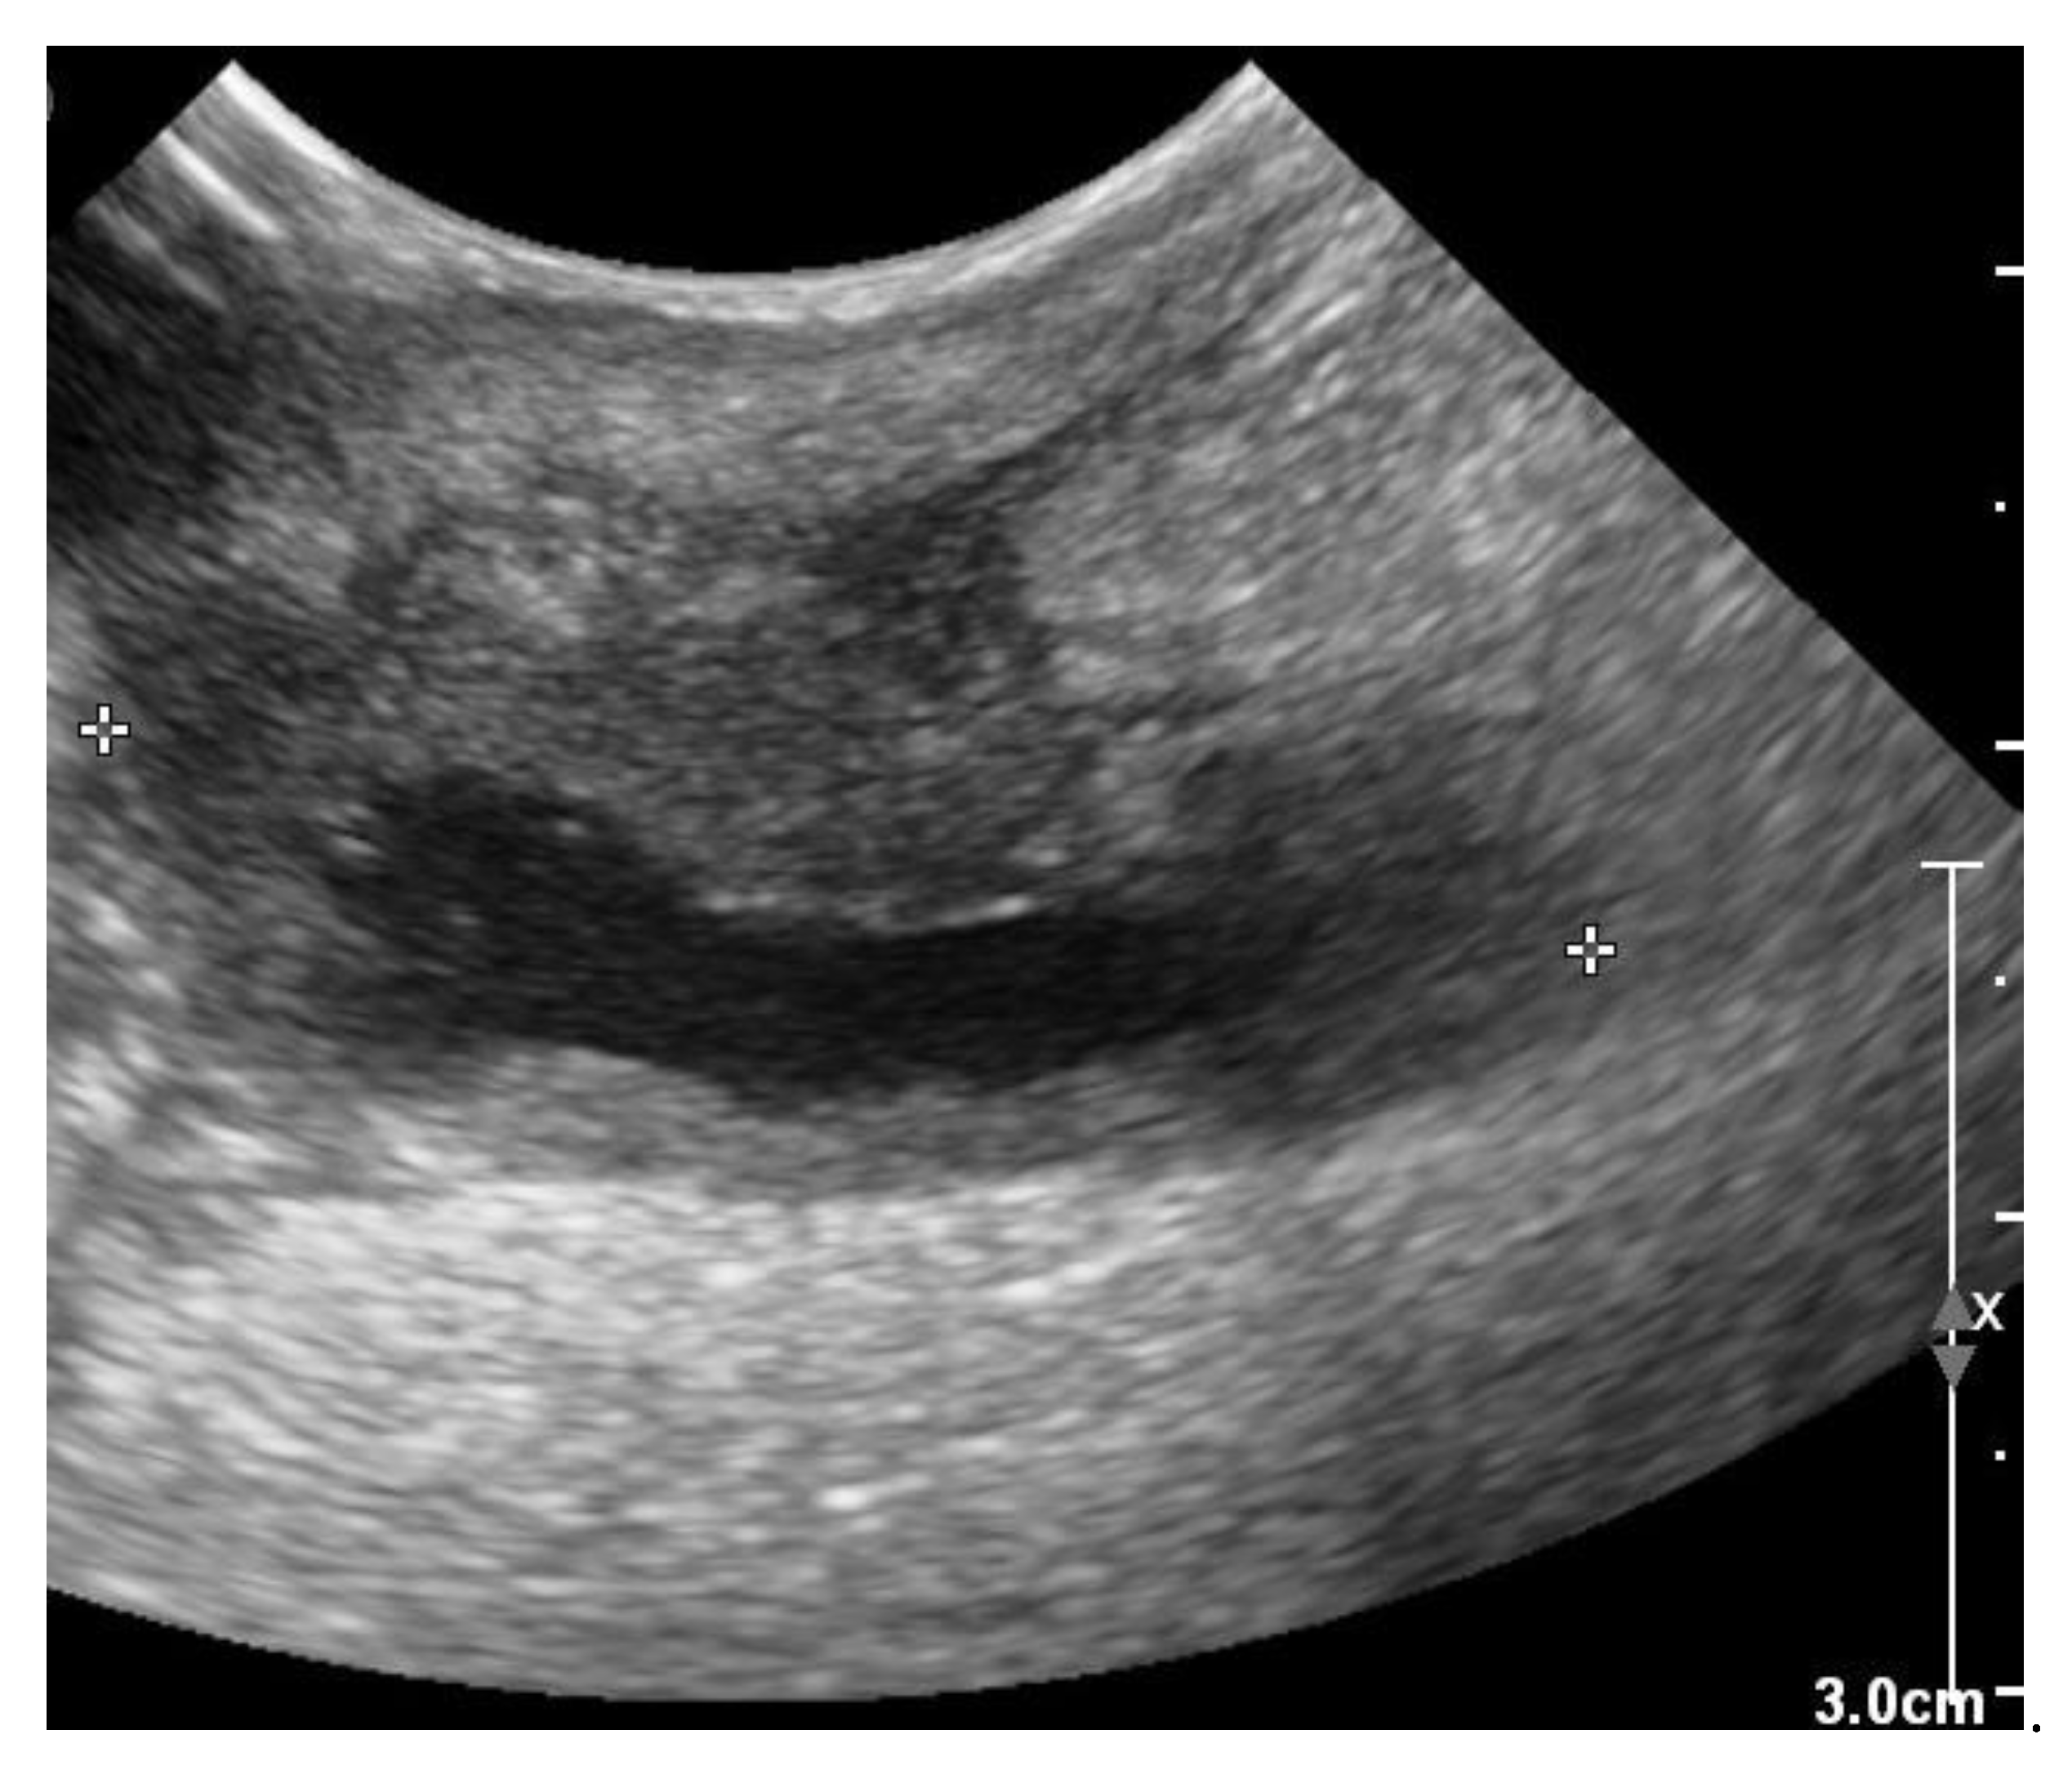

Three weeks after cessation of the oral antibiotic therapy, the dog became lethargic again and the owner noticed discharge from the previously healed cervical wound. The dog was presented again to the authors’ teaching hospital. Physical examination revealed a lethargic dog with a rectal temperature of 39.5 °C, and a warm and red lump of about 5 × 5 cm at the region of the previous surgical wound over the right jugular vein. In the skin overlying the lump, an opening of about 3 mm was visible, where purulent discharge was noticed. The dog was hospitalized again. Ultrasonographic examination of the lump was performed, which again identified a subcutaneous fluid pocket, but this time surrounded by a thick wall (Figure 7).

Figure 7. Two-dimensional grayscale ultrasonographic image of the swelling at the level of the previously healed surgical wound at the level of the jugular venous incision shows a pocket of fluid accumulation surrounded by abnormal soft tissue.